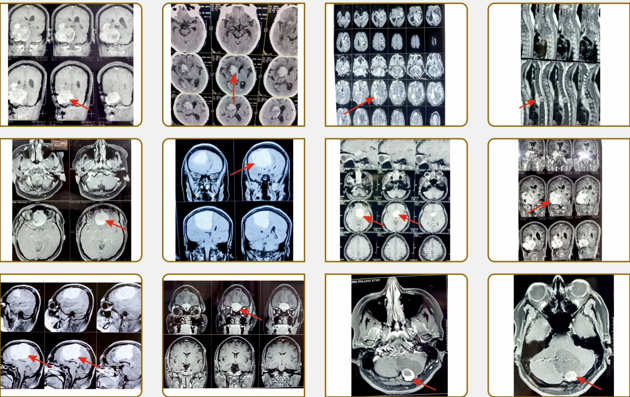

SPECTRUM OF NEUROSURGICAL INTERVENTIONS

1. Blood clots in the brain due to head trauma (injury) needs timely diagnosis and removal.

2. Diagnosis of Brain Tumors can be made before it can cause brain damage and these can be treated successfully.

3. Tumors of the spinal cord & spinal column can cause paralysis. Successful removal of these tumors and restoration of neurological function can be achieved.

4. Certain brain strokes need emergency blood clot removal from brain which can save life.

7. STEREOTACTIC Surgery of the brain helps to pinpoint and reach precise locations of small tumors and lesions in the brain.

9. Recently Navigation is widely used in Neurosurgery. This helps to plan trajectory and accurately approach the lesion in the brain while performing a brain operation.